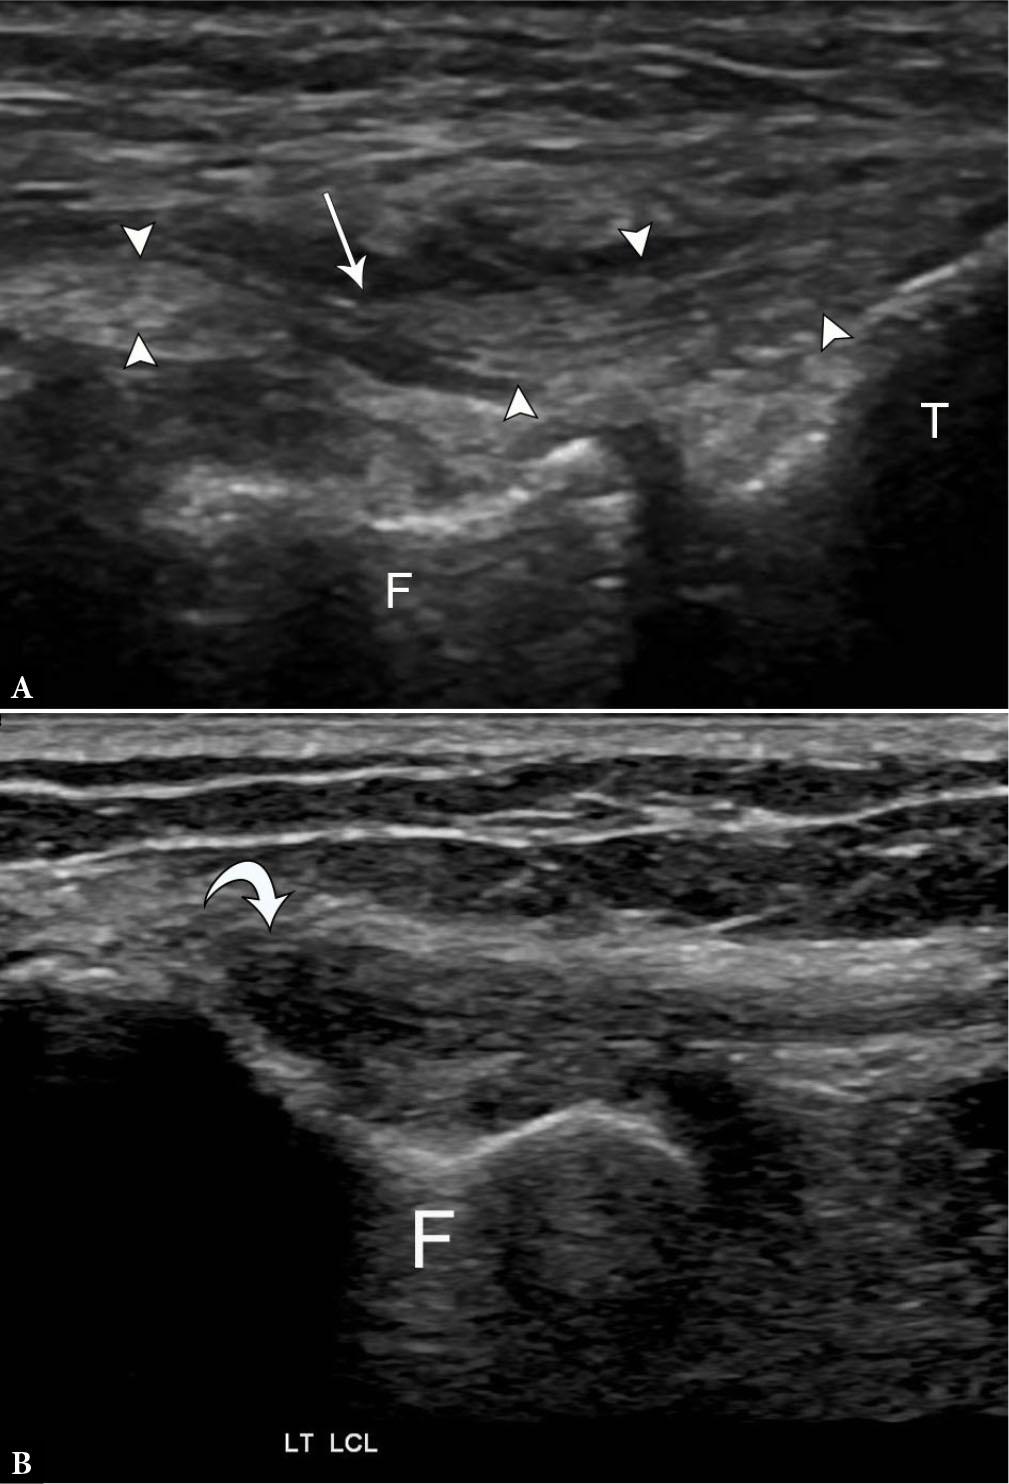

75-year-old female with high-grade partial fibular collateral ligament (FCL) injury. A. Longitudinal grayscale US image along the course of the FCL (arrowheads) next to the femoral popliteal groove (F) and tibial plateau (T) demonstrates attenuated remnant fibers with surrounding fluid (arrow). Compare to the normal appearance of the FCL on longitudinal grayscale US image B. with anisotropy (curved arrow) at the proximal portion